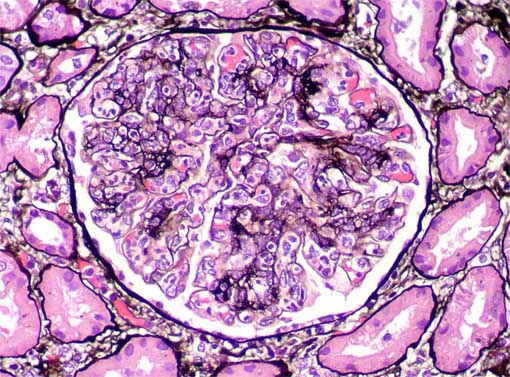

Figure 4.

Methenamine-silver stain, X400.